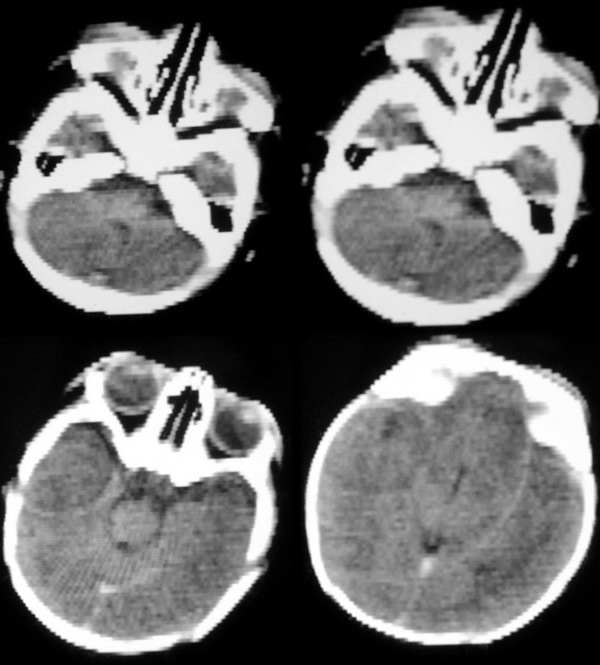

标题: CT2096:[求助]F ,3d, 因重度窒息入院余(--)。 [打印本页]

标题: CT2096:[求助]F ,3d, 因重度窒息入院余(--)。

多发脑水肿表现  考虑脑缺氧缺血脑病

结果:脑缺氧缺血脑病。其它的确是伪影,下午以经排除,真不好意思。幸好没误诊,谢谢分析对的战友!!